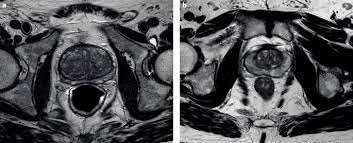

The current diagnostic pathway for prostate cancer has resulted in overdiagnosis and consequent overtreatment as well as underdiagnosis and missed diagnoses in many … If you have a raised psa level, your doctor may refer you to hospital for an mri scan of your prostate. Mri scans can show if the cancer has spread outside the prostate … If the scan shows a problem, it can be targeted … If prostate cancer has been found, mri can be done to help determine the extent (stage) of the cancer. Mri can not only confirm the presence of prostate cancer but pinpoint its location. 15.09.2021 · mri a valuable tool in early diagnosis and evaluation of the extent of tumors, such as prostate cancer. Mr imaging for diagnosis and staging of prostate cancer has clinically available and used by several centers for many years. 20.02.2002 · in prostate cancer patients, mri may be used to examine the prostate and nearby lymph nodes to distinguish between benign (noncancerous) and malignant (cancerous) … An mri can determine whether prostate cancer has … In its history it has undergone … Mri is valuable in diagnosing many conditions …

Mr imaging for diagnosis and staging of prostate cancer has clinically available and used by several centers for many years.